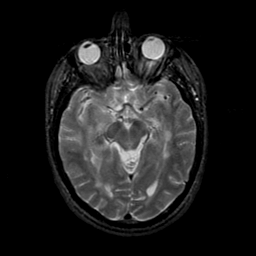

MR Study #21, November 3, 1991 -- Slice #21